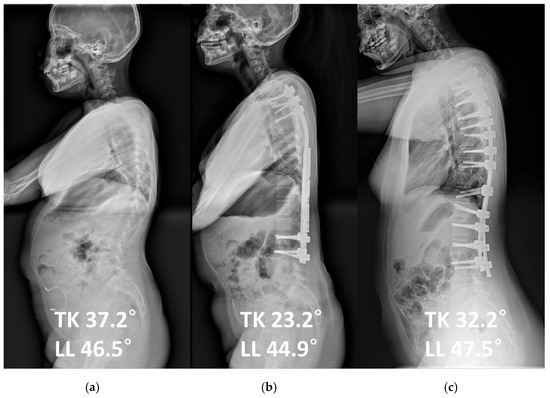

| Thoracic kyphosis (°) | 31.7 ± 17.4 | 34.5 ± 17.4 | 0.685 |

| Lumbar lordosis (°) | 48.8 ± 11.7 | 53.9 ± 22.6 | 0.480 |

| Thoracic kyphosis (°) | 28.4 ± 12.9 | 34.6 ± 10.6 | 0.268 |

| Lumbar lordosis (°) | 43.5 ± 15.2 | 49.0 ± 11.7 | 0.399 |

| Δ Thoracic kyphosis (°) | −11.9 ± 16.4 | 0.1 ± 11.9 | 0.088 |

| Δ Lumbar lordosis (°) | −4.3 ± 12.9 | −4.9 ± 19.8 | 0.942 |